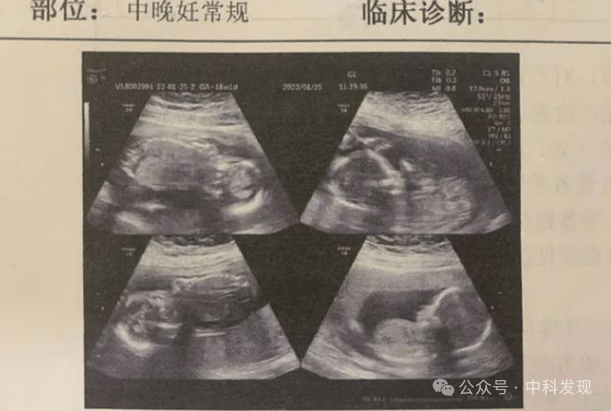

他们原本以为易重江怀的是个大胖小子,直到2003年3月的一次产检,才揭示了惊人的真相。

医生告诉他们,易重江怀的竟是四胞胎。这个消息让夫妇二人欣喜若狂。

四胞胎的出现概率极低,对他们而言就像是中了大奖一样。孩子们无疑是上天赐予的礼物,这个说法的确不假。